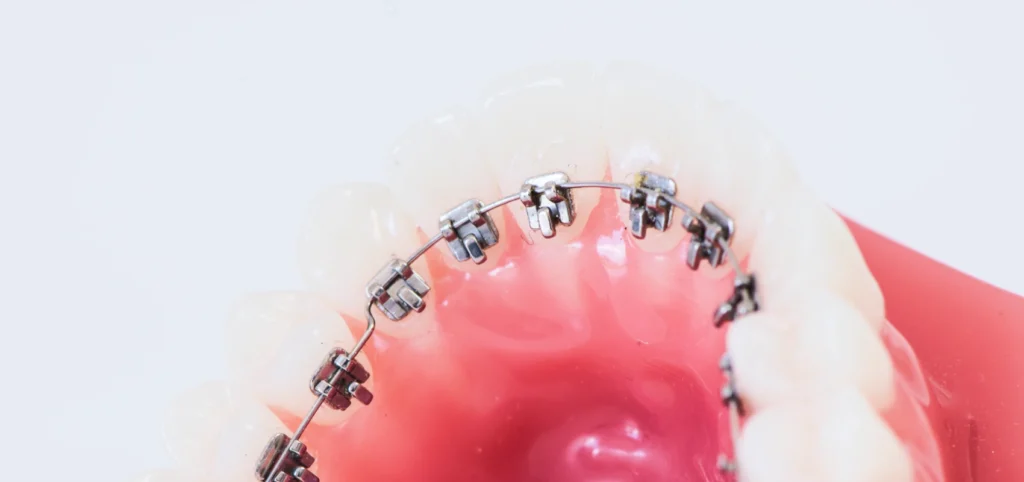

Appareils multi-attaches : efficacité et précision

Les appareils multi-attaches restent une solution fiable pour obtenir un résultat complet. Ils utilisent de petites attaches collées sur les dents, reliées entre elles par un fil métallique. Les attaches peuvent être métalliques ou en céramique pour plus de discrétion. Ce système permet un contrôle précis des mouvements dentaires et une correction complète de l’occlusion.